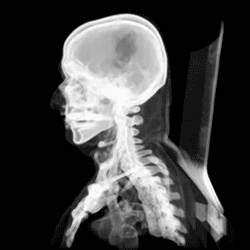

Computertomografi (fra det engelske computed axial tomography (CAT)), bedre kendt under forkortelsen CT og det afledte CT-skanning, er en avanceret form for røntgenundersøgelse, hvor diagnosticeringen sker ved hjælp af en række computerfremstillede tværsnitsbilleder (tomogrammer) af hoved, krop eller lemmer, der efterfølgende behandles digitalt, således at kropslige strukturer kan ses to- eller tredimensionelt.

Computertomografi blev oprindeligt kun brugt ved undersøgelser af hjernen, men anvendes i dag blandt andet andet ved undersøgelse af sygdomme i centralnervesystemet, ved diagnose og kontrol af kræft- og betændelsessygdomme, samt ved læsioner i hoved eller krop.

I modsætning til almindelige røntgenundersøgelser sendes røntgenstrålerne fra et røntgenrør, der roterer omkring det leje, patienten ligger på. Strålerne opfanges af sensorer, der registrerer deres styrke og sender dem videre til en computer. Strålingen er stærkere end ved almindelige røntgenundersøgelser, hvorfor CT-skanningen kun anvendes, når det er sygdomsmæssigt begrundet. Oftest anvendes et kontrastmiddel for at forbedre billedresultaterne.